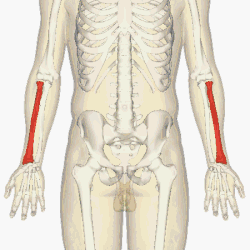

The radius (shown in red) is a bone in the forearm.

The radius or radial bone (pl.: radii or radiuses) is one of the two large bones of the forearm, the other being the ulna. It extends from the lateral side of the elbow to the thumb side of the wrist and runs parallel to the ulna. The ulna is longer than the radius, but the radius is thicker. The radius is a long bone, prism-shaped and slightly curved longitudinally.